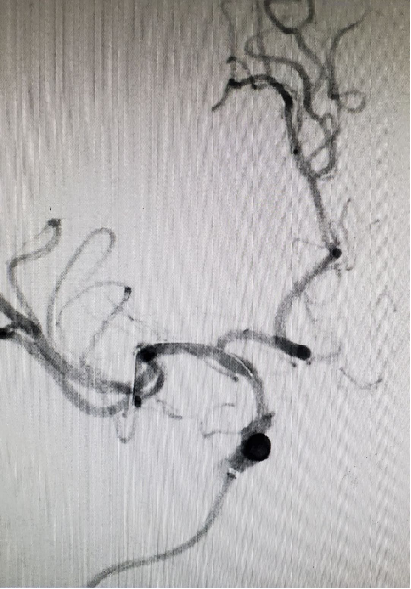

DSA:右侧颈内动脉正侧位

重要影像结论:右侧颈内动脉C6段狭窄约90%,长度约0.97cm。